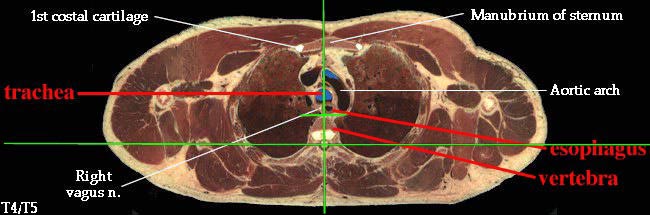

3. Describe the organization of the thoracic sympathetic trunk, in addition to its visceral and splanchnic branches. (W&B 413-416, N158, N160, N165, N209, N240, N254, TG4-45, TG4-46, TG8-03, TG8-14)This set of cross-sections might help (no guarantee!):

- Superior: plane b/w sternal angle and T4/T5

- Esophagus: enters the mediastinum a little to the right of the median plane, posterior to the trachea. It passes to the middle of the body, then to the left and anteriorly as it travels down to the stomach. (See "Extra Explanation" below.)